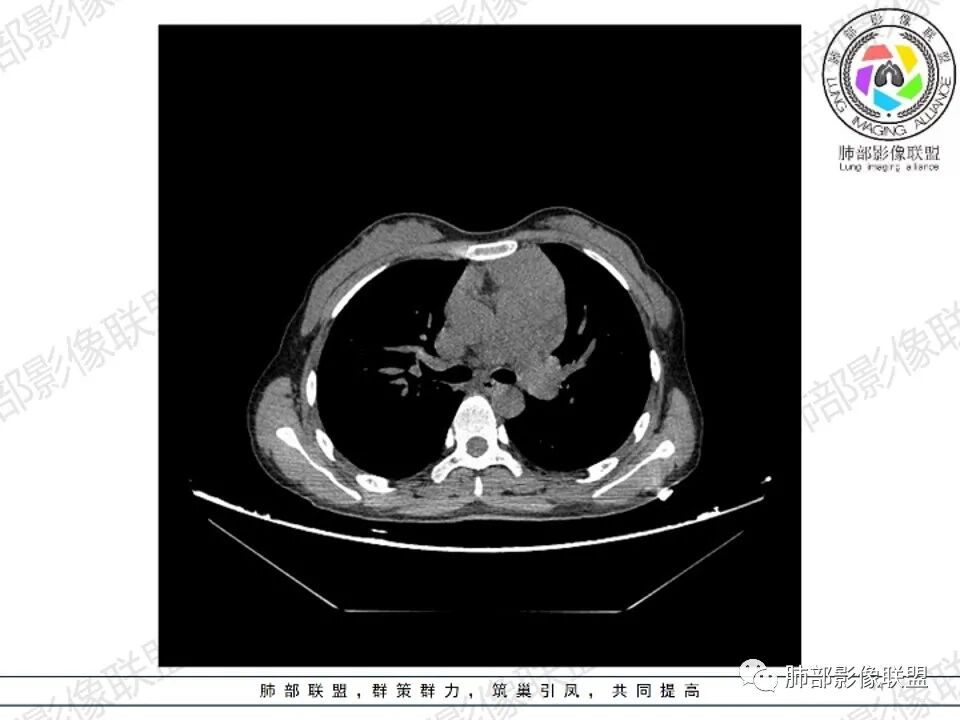

年轻女性,贫血,CT示前纵隔团片状软组织占位,多结节堆积感,塑形生长,边界欠清,包绕大血管及心包,增强明显不均匀强化,内见血管漂浮。纵隔4R,5,7区及双侧腋窝多发肿大淋巴结,综合考虑为淋巴瘤可能

前纵隔和双侧腋窝多发的淋巴结肿大,前纵隔为甚,融合呈中等强化,部分坏死呈低密度,包埋肺动脉主干和左心缘,融合斑块状,内见血管飘浮特点,前纵隔脂肪间隙混浊,首选淋巴瘤!